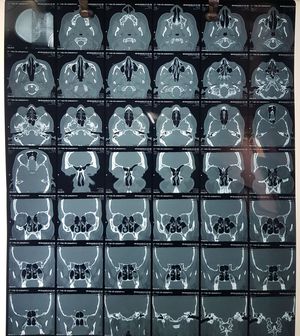

CT paranasal sinuses

ENT

Ct

Scan

Rhinosinusitis